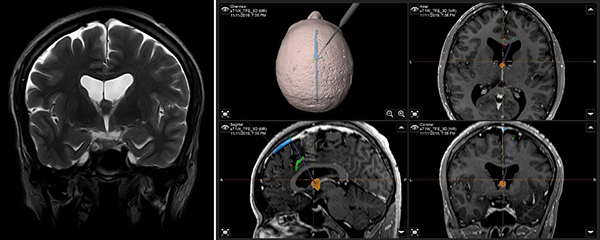

Figura 1. (A) IRM T2W coronal: ubicación anatómica de la lesión en foramen interventricular; (B) IRM integrada al sistema de neuronavegación, planeación de abordaje quirúrgico.

Paciente masculino de 40 años, sin antecedentes patológicos, atendido en nuestra institución por presentar cuadro de 2 años de evolución caracterizado por cefalea holocraneana de moderada intensidad, intermitente. Dos meses previo a la consulta inicial había presentado pérdida de consciencia más un episodio de crisis convulsiva tónico-clónico generalizada. Al examen físico el paciente no presentaba deterioro del sensorio ni déficit neurológico evidente. El resto del examen no mostraba hallazgos relevantes. La resonancia magnética (IRM) evidenció una lesión ovoidea que ocupaba el foramen de Monro, isointensa respecto al parénquima cerebral en las secuencias T1 y T2, de 12x9x9 mm, su margen rostral y dorsal en contacto con el pilar anterior y cuerpo del fornix, respectivamente; con tenue realce a la administración del contraste. En la secuencia de tensor de difusión los diferentes tractos se aprecian con trayecto normal y adecuada disposición de las fibras. Sistema ventricular sin dilatación ni compresiones. Se realizó la exéresis total de la lesión a través de un abordaje interhemisférico transcalloso anterior guiado por sistema de neuronavegación (Figura 1). El curso postoperatorio transcurrió con una hemiparesia braquio-crural derecha transitoria, que cede en días subsecuentes con recuperación total de la fuerza muscular. El paciente fue dado de alta sin déficit neurológico agregado. El examen patológico reportó un quiste coloide. La IRM postoperatoria confirmó la extirpación total de la lesión con cambios postquirúrgicos asociados a craneotomía fronto-parietal derecha (Figura 2). El paciente se encuentra asintomático en seguimiento por la consulta externa.

Figura 1. (A) IRM T2W coronal: ubicación anatómica de la lesión en foramen interventricular; (B) IRM integrada al sistema de neuronavegación, planeación de abordaje quirúrgico.